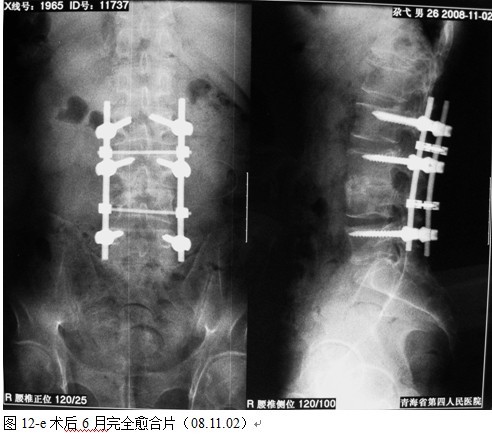

本组手术用时间3~4h , 平均3.5h 。术中出血300~500ml , 平均约350ml 。术后症状完全缓解,无神经功能障碍加重等并发症,1例营养差的老年患者伤口出现窦道,1例因肝功能差,术后未口服抗痨药,伤口出现窦道,经换药后二期愈合,其余病例伤口均一期愈合。马尾神经受损的患者术后基本恢复正常。术后一周后凸角平均 5.4°后凸畸形平均矫正90%以上, 最终后凸角平均8.3°,后凸角度平均丢失4.2°。随访3个月有87%(40/46)有骨痂形成,6个月91.3%(42/46)明显骨性愈合(见图),其余4例9-12个月内愈合,随访时间3-32个月,平均11个月,46例患者中2例在术后2个月和3个月时背部形成脓肿,换药后治愈。2例出院1月后并发结核性脑膜炎,治疗后好转。1例因椎弓根钉偏外,刺激神经根,5个月后从侧方脱出,疼痛加重,因前后路植骨完全愈合,取出后症状完全缓解。